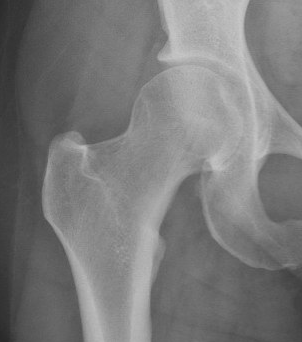

Tonnis grade 0 Tonnis grade 1 Tonnis grade 1